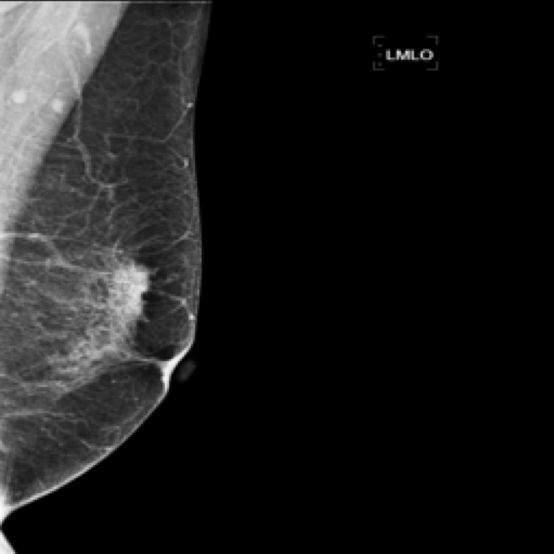

Mammography Imaging. In radiological examinations, multiple views are captured to thoroughly represent lesions. For mammography, these typically include four views: left mediolateral oblique (LMLO), left craniocaudal (LCC), right mediolateral oblique (RMLO), and right craniocaudal (RCC). To ensure dataset completeness and versatility for various tasks, we retained all views in their original form, irrespective of the presence breast lumps. However, views without breast lumps are not involved in this study.

5.9 ViKL Provides Evidence for Clinical Decision

In our earlier sections, we discussed how ViKL enhances the image branch’s capability for detailed feature extraction by using text and manifestations that describe localized lumps. To directly observe this enhanced feature extraction ability, we utilize the class activation map (CAM) [62], a common tool for visualizing neural network activations. Specifically, we employ Grad-CAM [63] to generate activation maps from the third layer of the ResNet50 model, which has been fine-tuned using ViKL on the MKVL dataset. Additionally, for accurate visualization and comparison, we include markings of lumps as annotated by professional radiologists. The results of this visualization are showcased in Fig. 6. These visualizations demonstrate ViKL’s effective localization of small lesions, highlighting its refined ability to capture minute features in medical imaging.